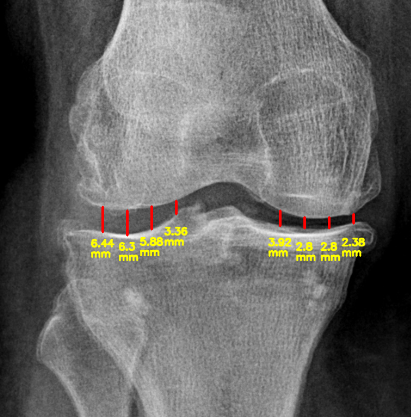

Calculating JSN

Developed an algorithm for calculating and visualizing Joint Space Narrowing (JSN) in knee images.